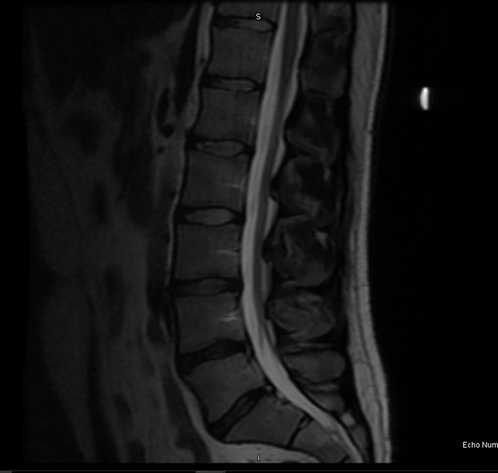

- Obtain a new MRI of the lumbar spine